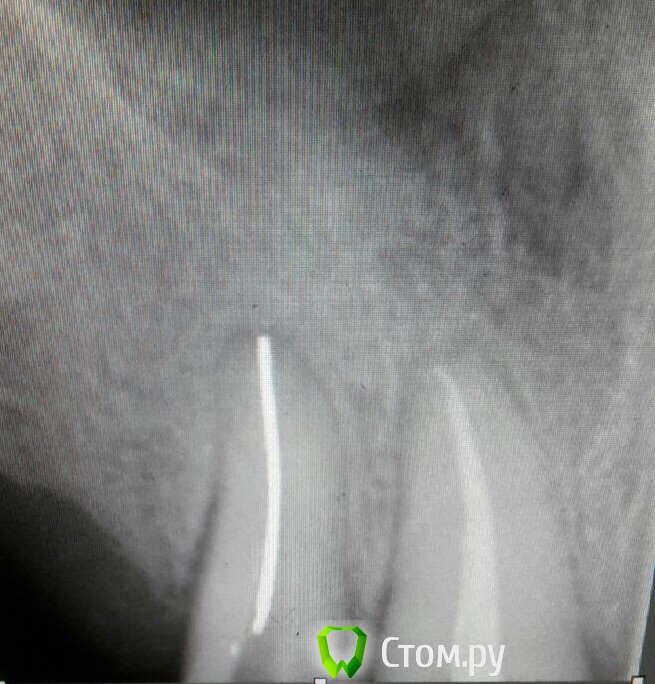

Stomka Опубликовано 9 ноября, 2013 Автор Поделиться Опубликовано 9 ноября, 2013 блин эндосаксесс это вещь) поищу) а силер я хз.. 14 лет назад лечен был зуб.. до перфы далеко.. зуб 11, rg контроль.. короч придется мучаться дальше) Сейчас я примерно на середине канала.. штифта осталось. ну мм 5 наверное) беда.. ох беда) Ссылка на комментарий

Catherine Опубликовано 21 октября, 2014 Поделиться Опубликовано 21 октября, 2014 (изменено) Файлом некрупным в эндочаке теребите его, освободите немного, далее работайте с водой, должен вымыться. 3-4 мм от края это не так глубоко, даже в 2,5 должно быть хорошо видноВот такой он "красавец" Изменено 21 октября, 2014 пользователем Catherine Ссылка на комментарий